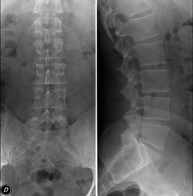

Técnica mediante la cual, utilizando rayos X, se obtienen imágenes del abdomen (estómago, intestino delgado, intestino grueso, hígado, riñones, vejiga, pelvis ósea, etc.) para su estudio. - RX Columna lumbar

Técnica mediante la cual, utilizando rayos X, se obtienen imágenes de la columna lumbar para su estudio. - TEGD (Tránsito Esófago – Gastro – Duodenal)

Técnica mediante la cual, utilizando rayos X, se obtienen imágenes de la columna dorsal para su estudio. Indicaciones: traumatismo, dolor de espalda. - RX Columna lumbar

Técnica mediante la cual, utilizando rayos X, se obtienen imágenes de la columna lumbar para su estudio. Indicaciones: ciática, traumatismo, dolor lumbar. - RX Sacro-cóccix